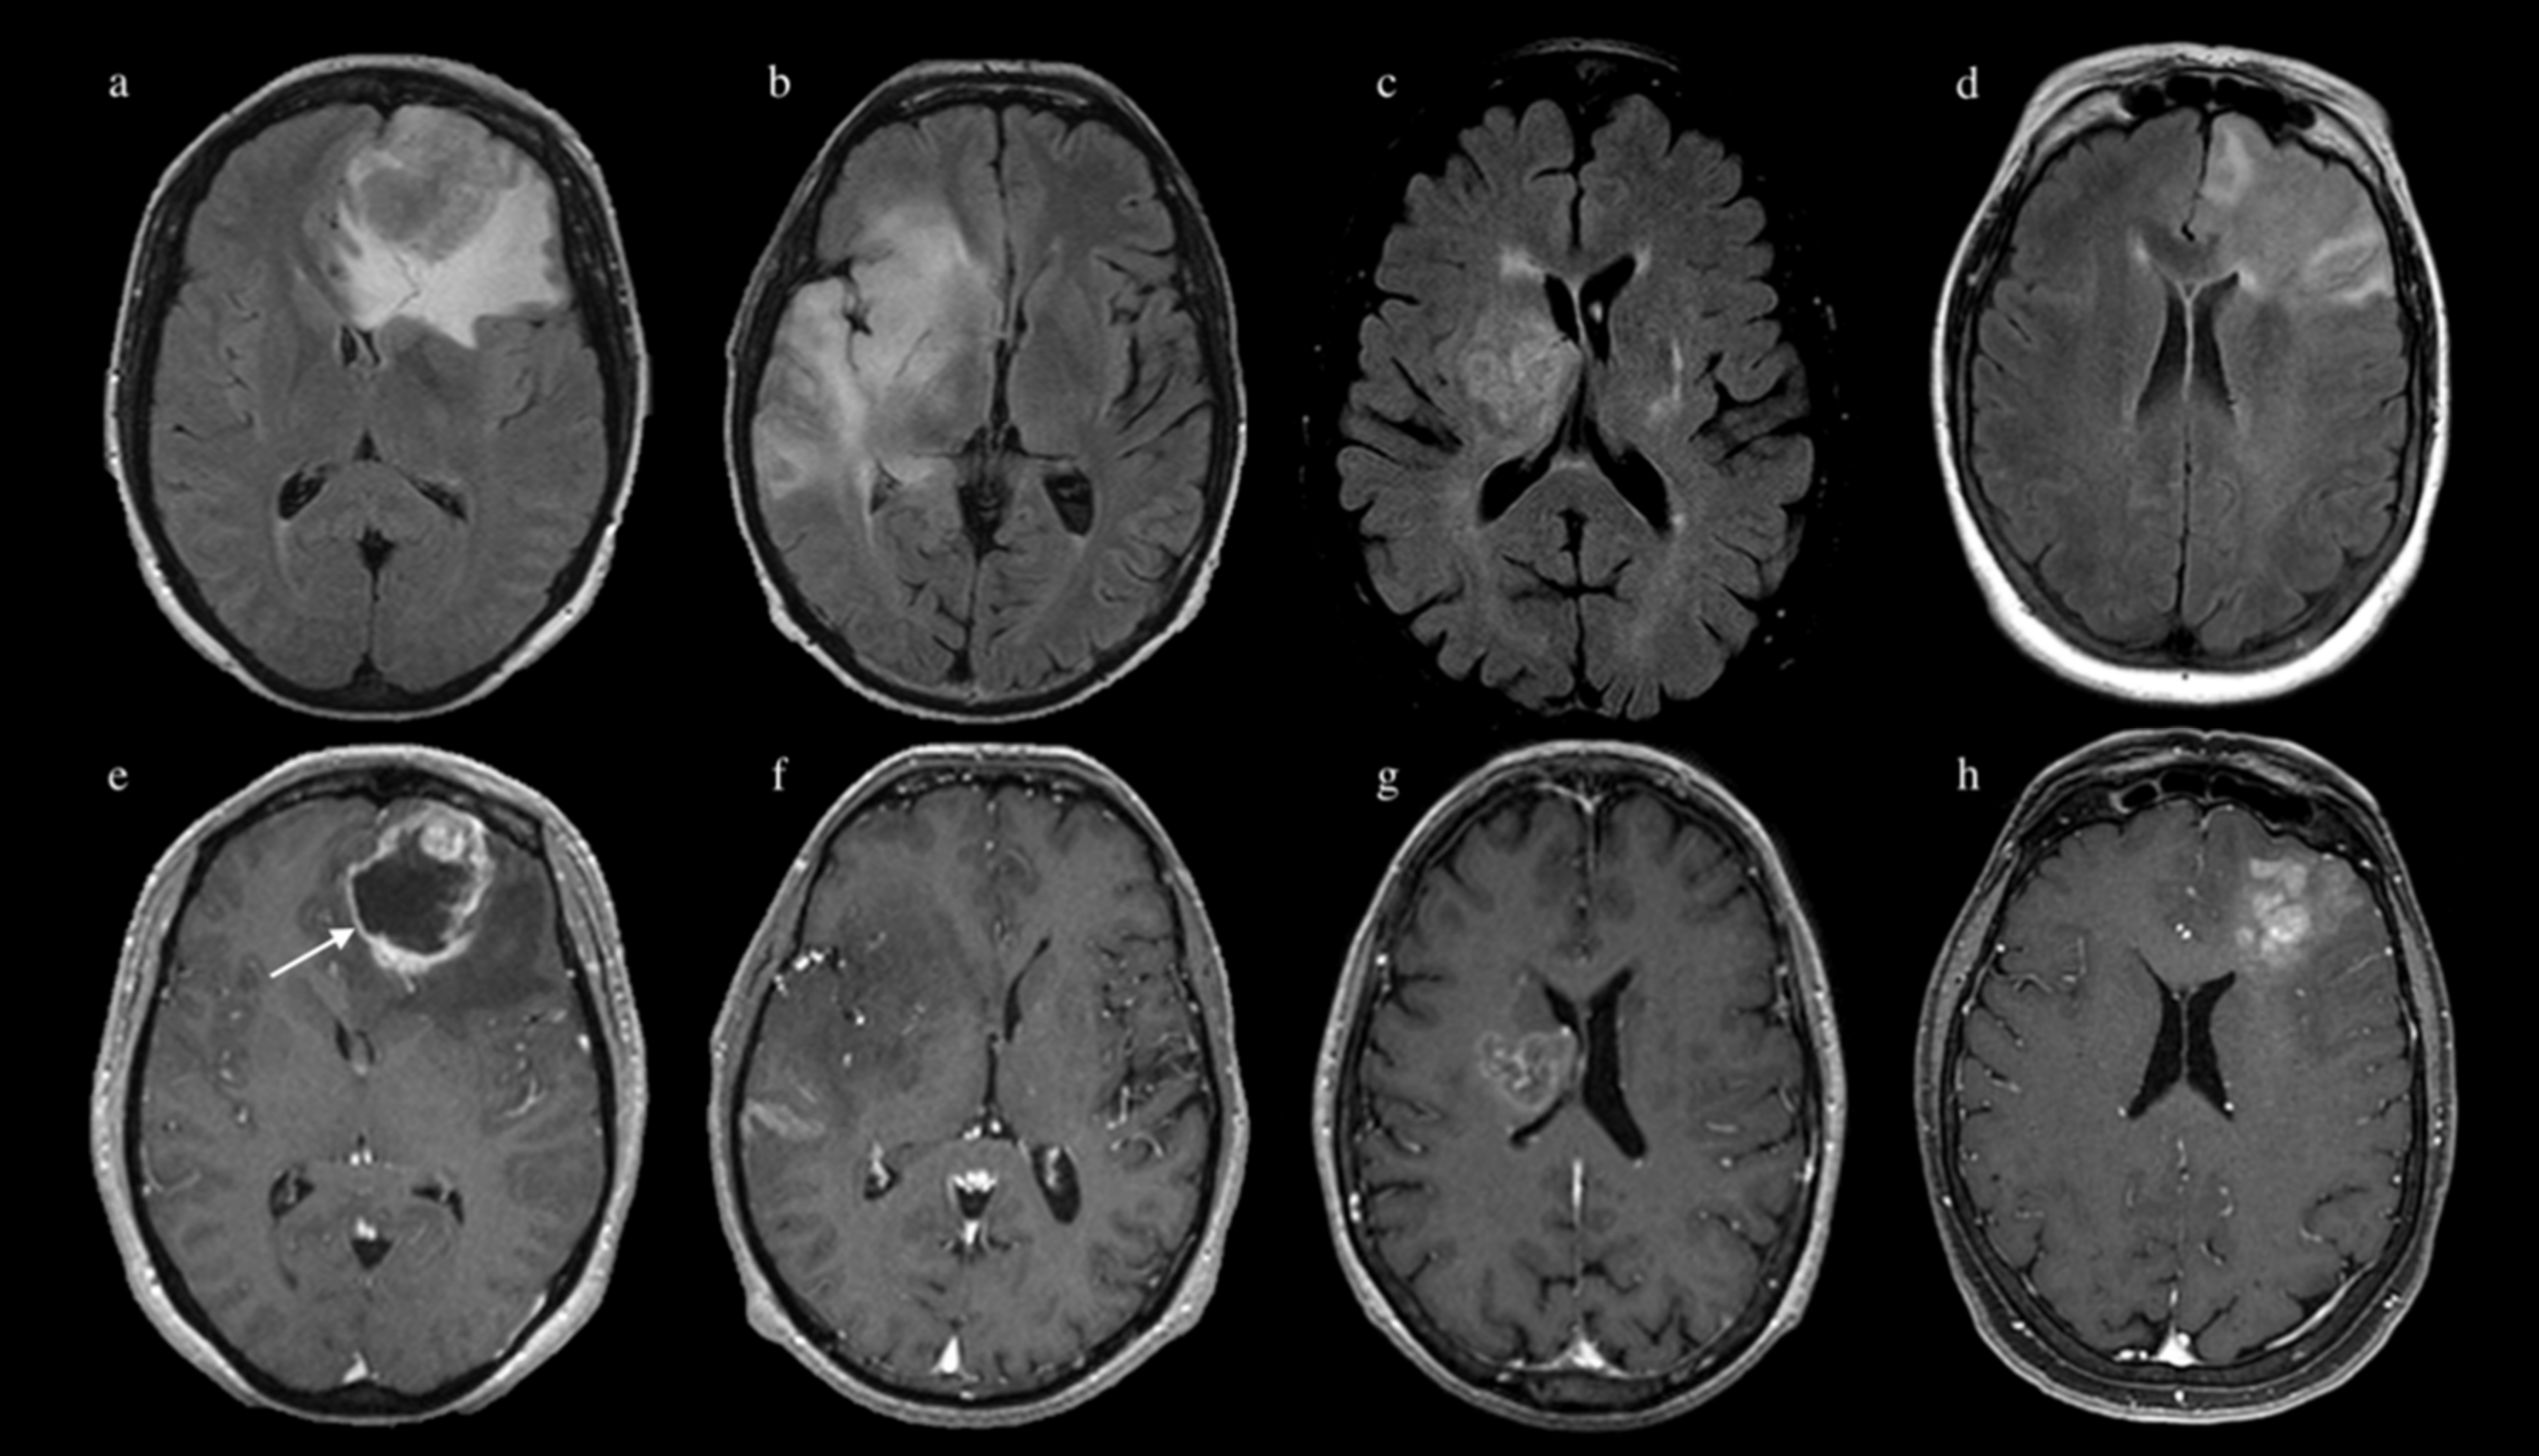

2. Materials and Methods

2.3. MR Image Acquisition

2.4. Image Processing